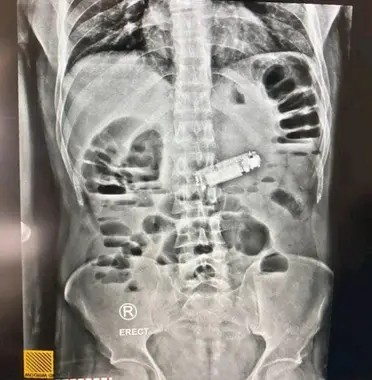

وكشفت الفحوصات الشاملة التي أجريت للمريض، والتي شملت الأشعة المقطعية والتحاليل الطبية، عن وجود جسم غريب يسد فتحة البواب في المعدة، تبين لاحقاً أنه هاتف محمول صغير الحجم.

وبعملية دقيقة استغرقت وقتاً قصيراً، تمكن الفريق الطبي من استخراج الهاتف بنجاح ودون مضاعفات، وتماثل المريض للشفاء سريعاً، حيث استعاد وعيه في قسم الإفاقة، وحالته الصحية مستقرة ويخضع حالياً للملاحظة الطبية.